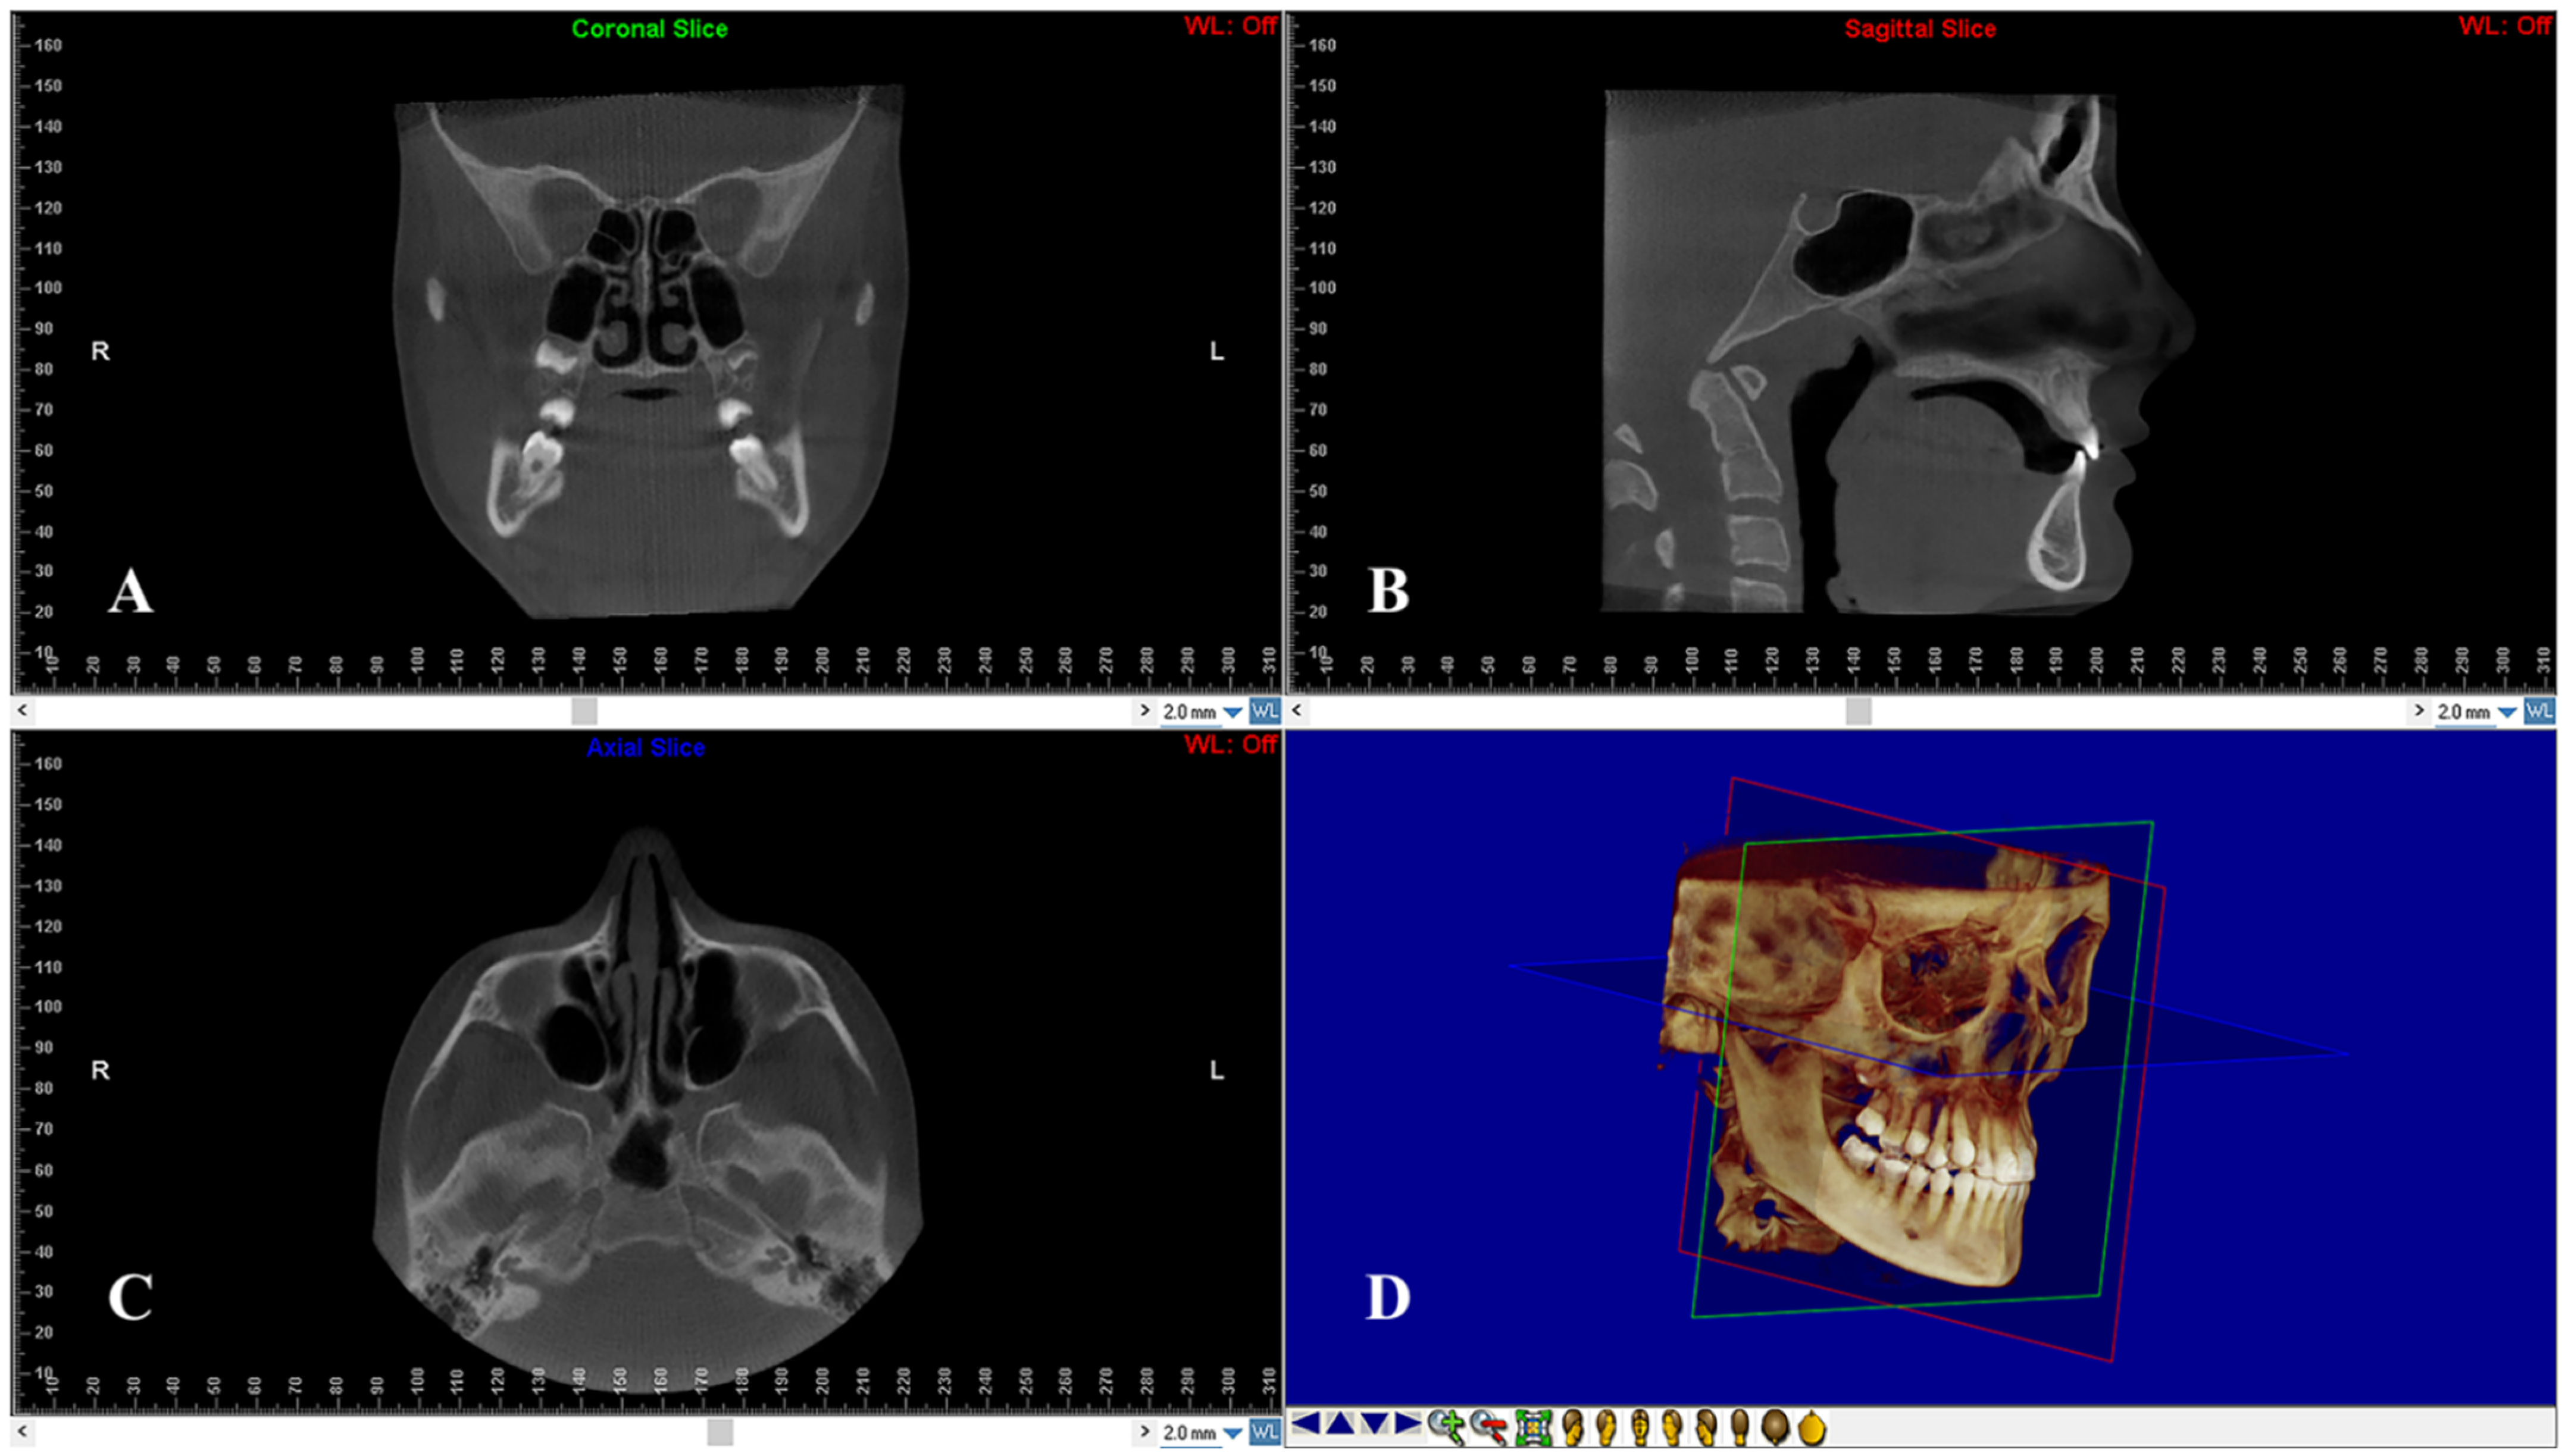

2.4. Skeletal Measurements

On multiple planar reconstruction images, the skull was reoriented to the Frankfort horizontal (FH) as follows (Figure 2): (1) in the frontal view, the mid-sagittal plane was fixed through the center of the anterior nasal spine (ANS), and the axial plane was constructed through both infraorbital skeletal landmarks; (2) in the right sagittal view, the axial plane was placed through the right porion and right infraorbital landmarks. For standardization, the left sagittal view was not processed to avoid orientation problems due to asymmetrically positioned portions; (3) in the axial view, the mid-sagittal plane was constructed through crista Galli and basion [23].

Figure 2.

Head re-orientation on coronal (A), sagittal (B) and axial (C) planes of CBCT scans. The 3D image (D) shows the head orientation on a 3D space.